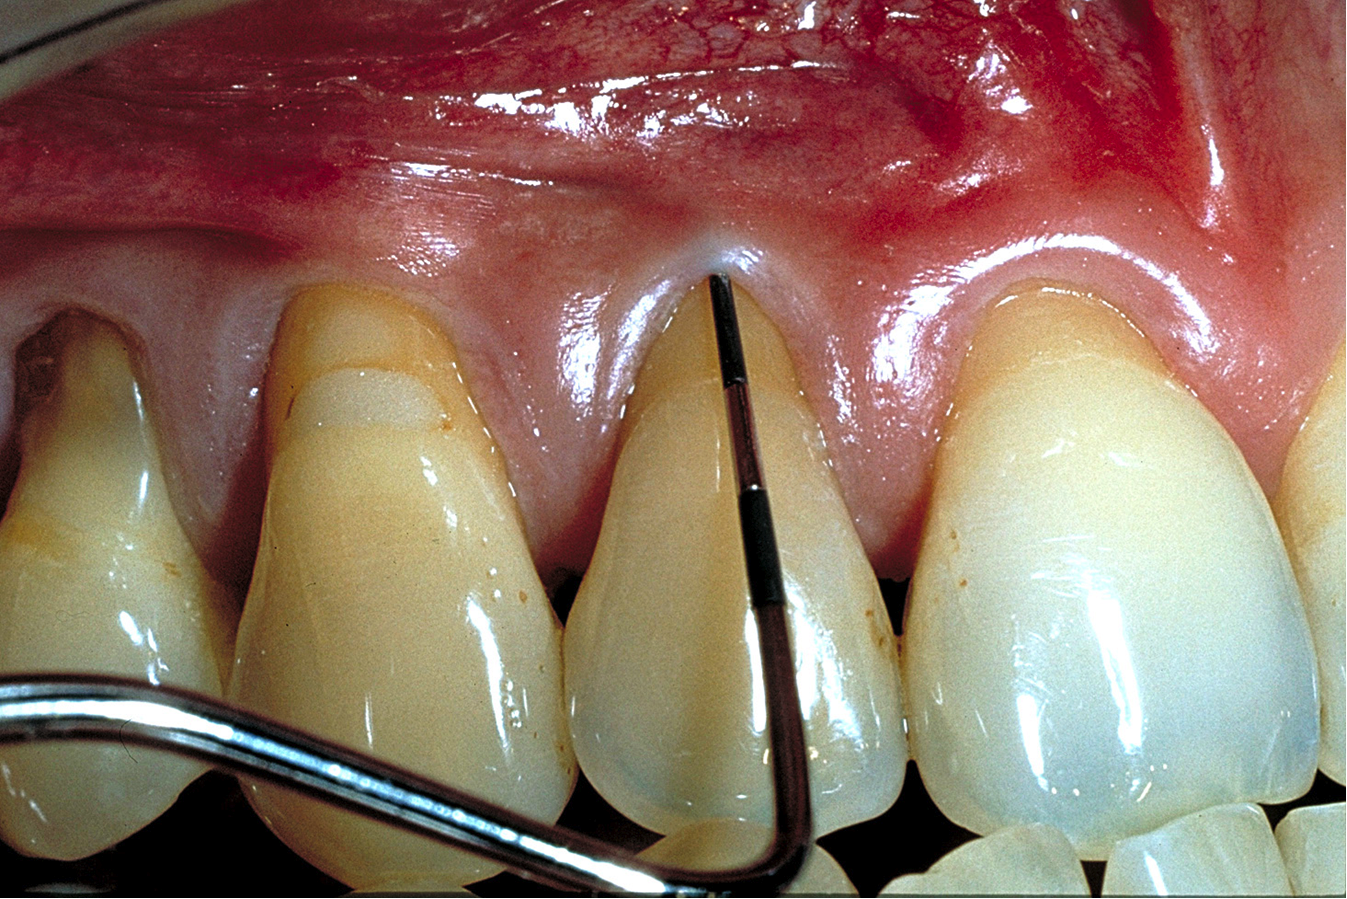

A patient presented with moderate recession requiring root coverage and increased thickness of the alveolar housing (Figure 9). A series of parallel incisions was completed using instruments made specifically for microsurgery; these incisions were performed utilizing high magnification (ie, 5.5 magnification via loupes). The distance between the incisions was roughly the amount of root coverage necessary on the adjacent teeth (Figure 10).25

The isthmus of tissue between the parallel incisions was removed. A split-thickness flap was elevated leaving connective tissue on the bone and providing access for root preparation.

To ensure a smooth root surface, rotary instruments with finishing burs and curettes are used. A glycine air-polishing unit (eg, Air-Flow Master, Hu-Friedy, hu-friedy.com) was used to impart the final smoothing of the roots and remove the smear layer and biofilm.